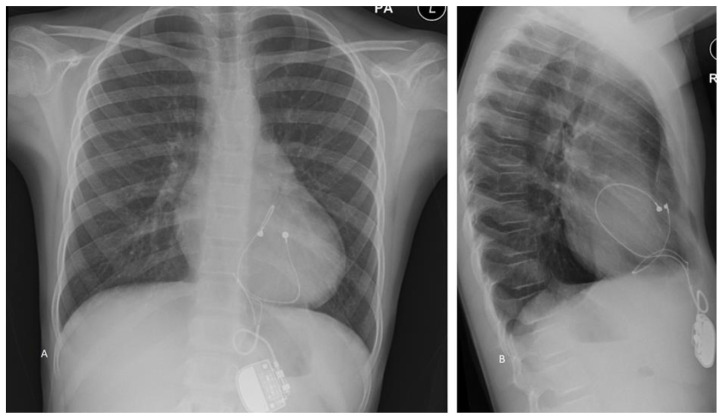

Cardiac strangulation is a rare but potentially lethal complication of epicardial pacemaker insertion. We present the case of a 9-year-old girl who was identified as having cardiac strangulation on routine follow-up for an epicardial pacemaker inserted on day 1 of life for congenital complete heart block (CCHB). The potential clinical presentations and risk factors for pacemaker strangulation are then discussed.